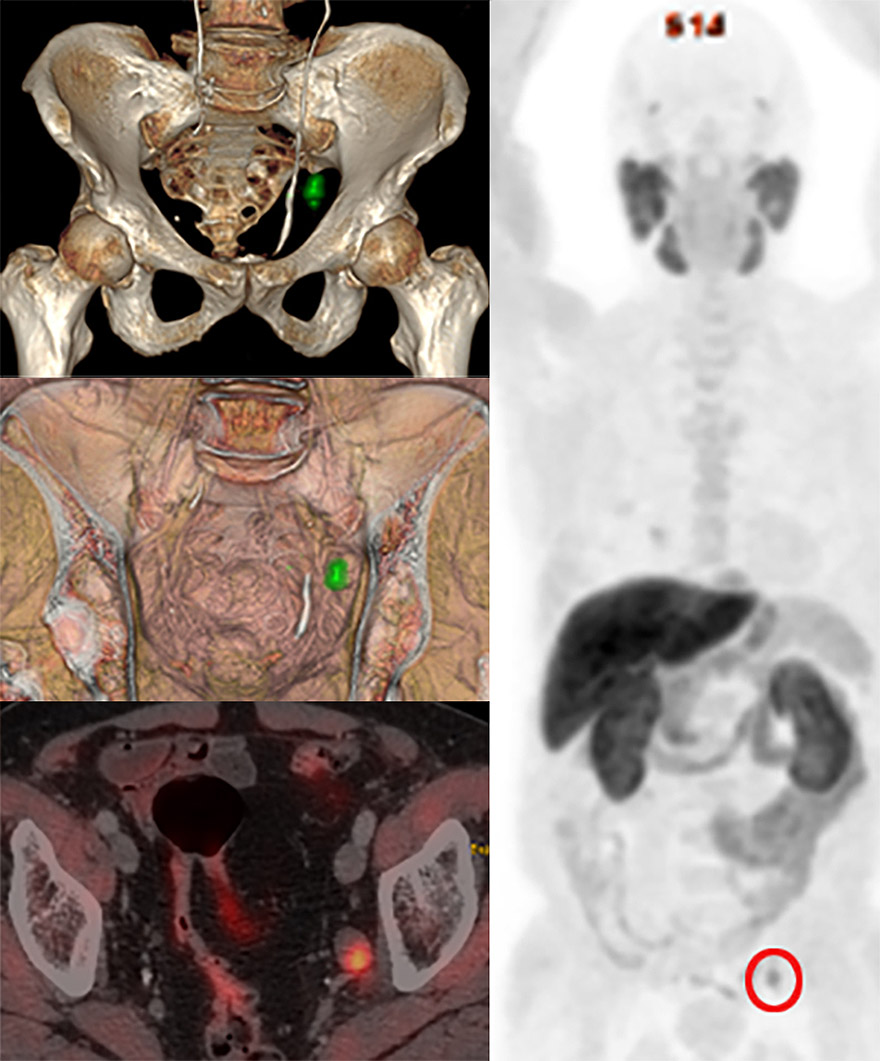

A todos estos radiofármacos se ha unido recientemente el 18F-PSMA, que permite detectar recaídas en cáncer de próstata incluso con niveles de antígeno prostático (PSA) muy bajos lo que ha cambiado la actitud terapéutica frente a estos pacientes y la detección de las recidivas mucho antes lo que mejora su pronóstico.

En un 49.1% de los estudios durante esta década se utilizó la 18F-Colina y en un 30.9% el 18F-Beta-amiloide. Entre las indicaciones más relevantes por su impacto en el manejo de los pacientes está el uso de la 18F-COLINA en la detección de adenomas de paratiroides previo a cirugía radioguiada tipo ROLL y el 18F-PSMA en la detección de recidiva bioquímica del cáncer de próstata. En ambos casos, la prueba PET-CT se realiza cuando los protocolos habituales no detectan patología, mostrando en ambas situaciones clínicas una elevada rentabilidad diagnóstica (90-95% en la detección precoz del adenoma de paratiroides entre un 40 y un 70% en la detección temprana de la recaída del cáncer de próstata).